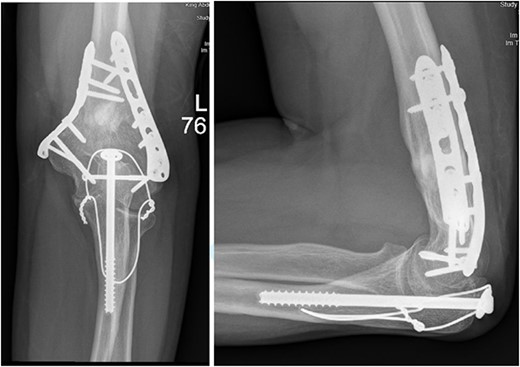

Upon arrival the patient underwent exploratory laparotomy followed by irrigation and debridement of both femur and humerus and application of external fixators (Fig. 2). The patient was admitted to the intensive care unit (ICU). Two days later, the patient underwent open reduction and internal fixation of both proximal and distal humerus (Fig. 3).

Anteroposterior (AP) view of the left humerus and elbow after Ex-fix application.

Anteroposterior (AP) view of the left humerus and elbow after ORIF.